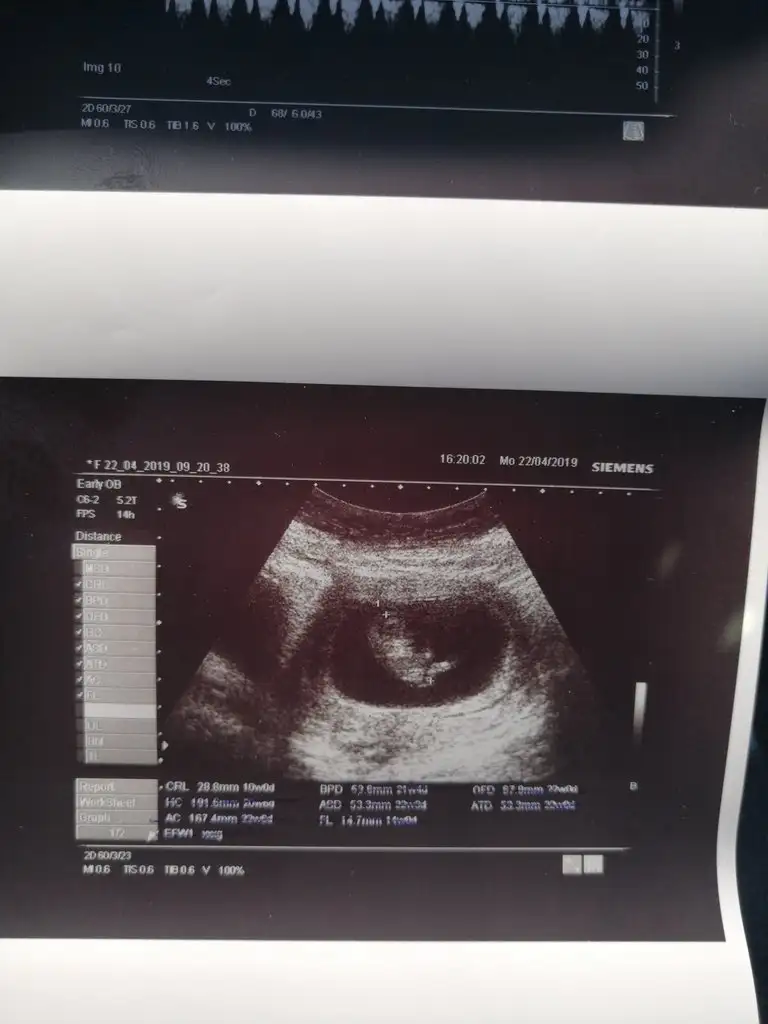

Kızlar Allahıma cok şükür benim bebi büyümüş. 3.8cm olmuş. 4 gün de ileri atmış. 10+5 olduk benim kalp atışım heyecan ve stresten 105 cıktı o yüzden bebeginki de 192 cıktı. Dr 5 dakika sakinleş tekrar ölcücem dedi. 181 e indi bebegin kalp atışı. Bu arada beslenmesinde bir şey hosuna gitmedi o yüzden enox 0.4 baslattı. Cinsiyet goremedik, haftaya salı ikili tarama ve cinsiyete tekrar bakarız dedi. Rabbim hepimize saglıklı bebekler nasip etsin.